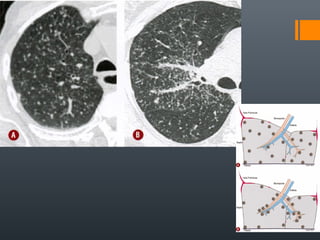

O documento discute vários conceitos radiológicos incluindo consolidação, atelectasia, nódulos, pseudocavidades e padrões intersticiais, fornecendo definições, sinais e diagnósticos diferenciais para cada tópico. Ele também discute a redução da atenuação pulmonar e fornece um link para mais informações.